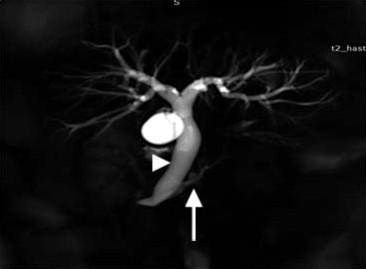

An USG abdomen showed mild hepatomegaly with extrahepatic biliary dilatation and periampullary mass. MRI and MRCP abdomen revealed dilated intra and extra hepatic bile ducts with narrowing of distal CBD with periampullary mass (Figures 1 and 2). MRI abdomen also showed hypoplasia of body and tail of the pancreas suggestive of agenesis of dorsal pancreas (Figure 2). ERCP was done and put biliary stent.

Figure 1. MRCP Image showing dilated common bile duct (arrow head) with short main pancreatic duct (arrow) suggestive of agenesis of dorsal pancreas. |